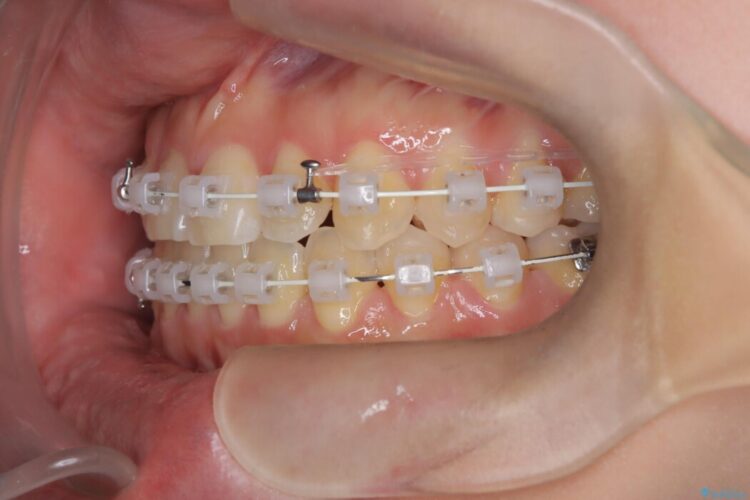

- 矯正装置:審美装置

ワイヤーで歯列を矯正しつつ、癖などによる口腔習癖も改善することにより切端咬合を治していく計画を立てました。